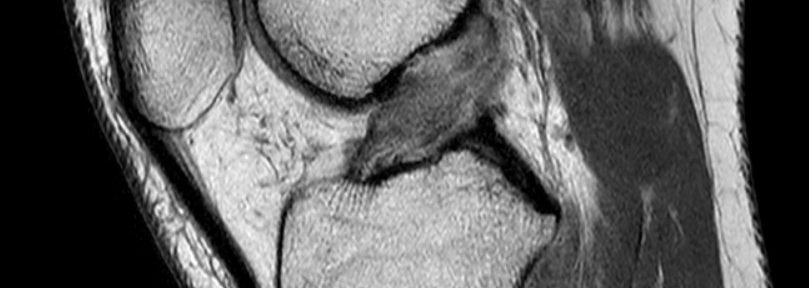

Caso 50 | Rigenerazione Naturale del LCA: Dalla Grave Rottura Ihara IV alla Perfezione Strutturale (ACLOAS 0)